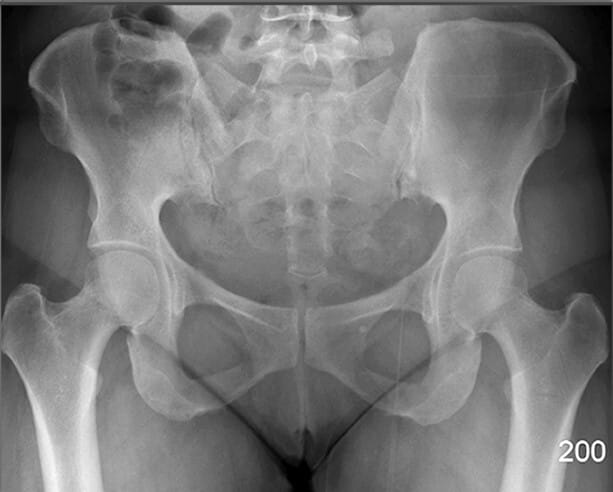

Bony Structures (AP View)

천골 (Sacrum)

| 천골 (Sacrum) |

| ✅ 요추 아래에 위치하며, 미골과 연결되는 큰 삼각형 구조입니다. AP view에서 정중앙 하부에 넓은 골 구조로 관찰됩니다. |

| 🔴 천장관절(sacroiliac joint)의 기준이 됩니다. |

미골 (Coccyx)

| 미골 (Coccyx) |

| ✅ 척추의 가장 하단에 위치한 작은 골절 구조로, 천골 아래에서 정중앙에 위치합니다. |

| 🔴 AP view에서는 짧고 좁은 골 구조로 보이며, 미골 통증(coccydynia)이나 외상 평가 시 주요하게 봐야 합니다. |

장골 (Ileum)

| 장골 (Ileum) |

| ✅ 골반의 상부를 구성하는 큰 뼈로, 장골능(iliac crest)과 전상장골극(ASIS) 등을 포함합니다. |

| 🔴 AP view에서는 넓은 곡선형 음영으로 관찰되며, 골반 골절 여부 평가에 중요합니다. |

장골능 (Iliac Crest)

| 장골능 (Iliac Crest) |

| ✅ 골반의 가장 상부 경계로, AP pelvis 영상에서 양측 상단에 대칭적으로 보입니다. |

| 🔴 곡선을 이루며, 체위 기준점으로도 활용됩니다. |

좌골결절 (Ischial Tuberosity)

| 좌골결절 (Ischial Tuberosity) |

| ✅ ‘앉는 뼈’라고도 불리는 부위로, 체중이 걸리는 지점입니다. AP pelvis 영상에서 골반의 가장 하단에 큰 음영으로 보입니다. |

| 🔴 햄스트링 기시부위로 근육 손상 및 견열골절이 발생할 수 있는 부위입니다. |

좌골극 (Ischial Spine)

| 좌골극 (Ischial Spine) |

| ✅ 골반 내측 벽에 위치한 뾰족한 돌기 구조로, AP view에서 천골 양측 근처에 미세한 돌출로 관찰됩니다. |

| 🔴 산과적 평가(산도 협착 등)에서 중요한 해부학적 지표입니다. |

전하장골극 (Anterior Inferior Iliac Spine)

| 전하장골극 (Anterior Inferior Iliac Spine) |

| ✅ 장골의 전면 하부에서 돌출된 골격 구조로, AP pelvis 영상에서 양측 장골의 앞쪽 경계선 부근에 위치합니다. |

| 🔴 대퇴직근(rectus femoris)의 기시부로 기능하며, 외상 시 견열 골절(avulsion fracture)이 발생할 수 있습니다. |

치골체 (Body of Pubis)

| 치골체 (Body of Pubis) |

| ✅ 골반 전면 중앙을 구성하는 뼈 구조로, 치골결합(pubic symphysis)의 양측에서 관찰됩니다. |

| 🔴 골반의 안정성과 관련된 부위로, 골절이나 결합 이완 여부를 평가할 때 중요합니다. |

치골결합 (Pubic Symphysis)

| 치골결합 (Pubic Symphysis) |

| ✅ 치골의 정중앙에서 좌우를 연결하는 섬유연골 관절로, AP view에서 골반 중앙 하단에서 좁은 간격의 음영으로 보입니다. |

| 🔴 외상이나 분만 후 이완이나 분리(pubic diastasis)가 발생할 수 있습니다. |

치골결절 (Pubic Tuberosity)

| 치골결절 (Pubic Tuberosity) |

| ✅ 치골의 상단에서 약간 돌출된 부위로, AP view 에서는 치골결합 바로 옆에서 작고 밀도 높은 음영으로 보입니다. |

| 🔴 인대 부착 부위로 해부학적 기준점으로 활용됩니다. |

상치골지 (Superior Pubic Ramus)

| 상치골지 (Superior Pubic Ramus) |

| ✅ 치골의 상단 분지로, 치골결합에서 대각선으로 위쪽으로 뻗어 장골과 연결됩니다. AP View에서는 골반 앞쪽 상부에서 연속적인 골 음영으로 나타납니다. |

| 🔴골반 고리의 안정성을 평가하는데 중요한 구조입니다. |

하치골지 (Inferior Pubic Ramus)

| 하치골지 (Inferior Pubic Ramus) |

| ✅ 치골의 하부 분지로, 좌골과 연결되어 골반 하부를 구성합니다. AP view에서 치골결합 아래쪽에서 대각선 방향으로 연장된 음영으로 나타납니다. |

| 🔴 외상성 골절이 흔히 발생하는 부위입니다. |

Pelvic Region

PELVIS

비구 (Acetabulum)

| 비구 (Acetabulum) |

| ✅ 대퇴골두(femoral head)가 삽입되는 골반 측면의 오목한 부분으로, AP view에서 둥근 원형 구조로 나타납니다. |

| 🔴골절, 탈구, 또는 관절 간격 이상이 있는지 확인하는 것이 중요합니다. |

전상장골극 (ASIS, Anterior Superior Iliac Spine)

| 전상장골극 (ASIS, Anterior Superior Iliac Spine) |

| ✅ 장골의 앞쪽 윗부분에 돌출된 뼈로, AP view에서 골반의 가장 상전방에 대칭적으로 위치합니다. |

| 🔴 표면해부학에서 중요한 구조로 , 골반의 변위를 대략적으로 파악할 수 있습니다. |

폐쇄공 (Obturator Foramen)

| 폐쇄공 (Obturator Foramen) |

| ✅ 치골과 좌골 사이에 위치한 크고 타원형의 개구부로, AP view에서는 골반 하단 양측에 대칭적인 투과성 음영으로 보입니다. |

| 🔴 골반 골절에서 비대칭이나 모양 변화가 나타날 수 있는 부위입니다. |

골반 입구 (Pelvic Inlet)

| 골반 입구 (Pelvic Inlet) |

| ✅ 천골 윗면에서 치골결합까지 이어지는 경계로, 출산 시 태아가 처음 통과하는 공간입니다. |

| 🔴 AP view에서는 전체 골반 윤곽과 함께 전후 직경을 간접적으로 추정할 수 있습니다. |

천장관절 (Sacroiliac Joint)

| 천장관절 (Sacroiliac Joint) |

| ✅ 천골과 장골 사이의 관절로, AP view상에서 좌우 대칭적으로 좁고 긴 틈으로 관찰됩니다. |

| 🔴 간격이 좁아지거나 불규칙한 경우 염증성 질환(예: 강직성 척추염)을 의심할 수 있습니다. |

FEMUR

대퇴골두 (Head of Femur)

| 대퇴골두 (Head of Femur) |

| ✅ 비구에 삽입되어 고관절을 이루는 구형 구조물로, AP view에서 관절 중심부의 둥근 음영으로 나타납니다. |

| 🔴 대퇴골두의 위치와 관절 간격을 통해 탈구, 골괴사 등을 평가할 수 있습니다. |

대퇴골 경부 (Neck of Femur)

| 대퇴골 경부 (Neck of Femur) |

| ✅ 대퇴골두와 대퇴골 간부 사이의 연결 부위로, AP view에서 비구 아래 대각선으로 위치한 가늘고 길쭉한 구조입니다. |

| 🔴 노인의 고관절 골절이 자주 발생하는 부위로, 윤곽 변화나 불연속성을 신경 써서 관찰해야 합니다. |

대전자 (Greater Trochanter)

| 대전자 (Greater Trochanter) |

| ✅ 대퇴골의 외측 상부에 위치한 크고 돌출된 구조로, AP view에서 고관절 외측에 명확한 골 음영으로 나타납니다. |

| 🔴 고관절 주위 근육의 부착점이며 외상 시 골절 부위가 될 수 있습니다. |

소전자 (Lesser Trochanter)

| 소전자 (Lesser Trochanter) |

| ✅ 대퇴골의 후내측에 위치한 작은 돌기이며, AP view에서는 보통 대퇴골 내측에서 작고 조밀한 음영으로 관찰됩니다. |

| 🔴 굴곡근(Hip Flexor)의 부착점이며, 과사용성 견열 손상이 발생할 수 있습니다. |